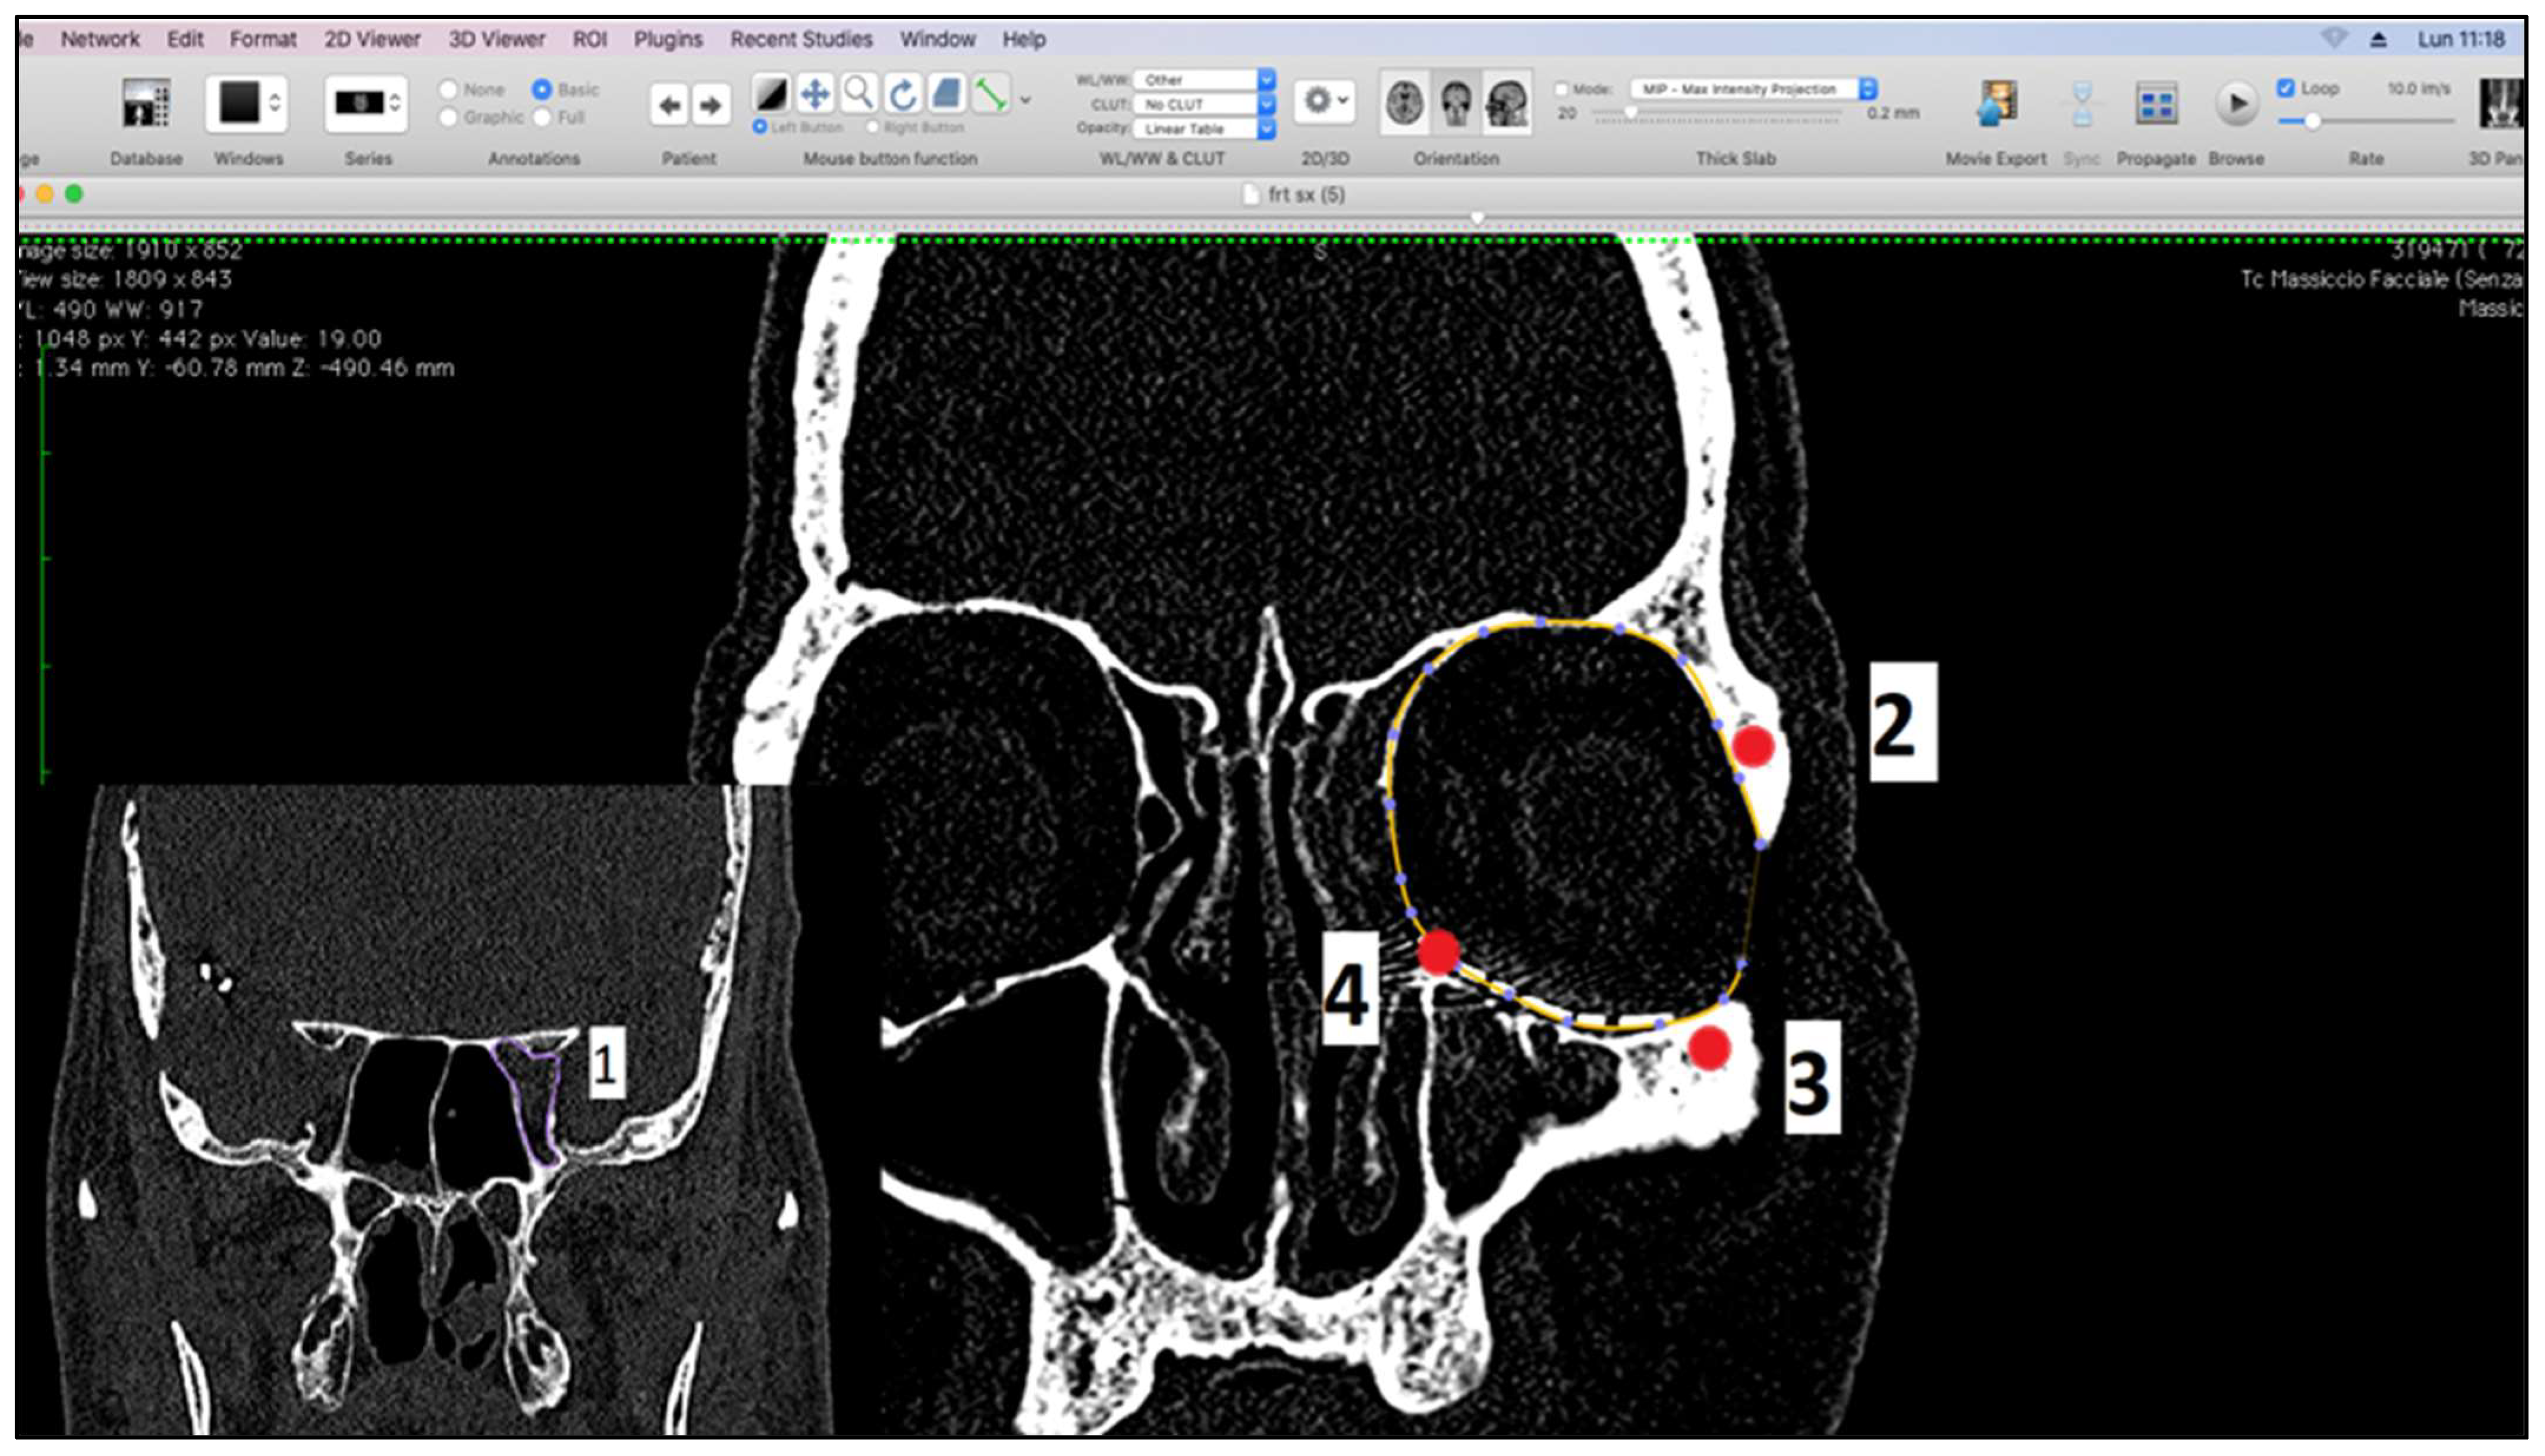

2.2. Measurement of Orbital Volumes

We performed the measurements using Osirix software in semi-automatic and manual mode on CT scans [17,18], on both preoperative and postoperative CT examinations, with slices of 0.5 mm and with the head positioned in its “neutral position”. Preoperative CT was carried out within 24 h of the trauma. We corrected the minimal movement discrepancies using the MPR function of the software with anatomical references in the planes: the Frankfurt horizontal plane, a vertical plane passing between the supraorbital foramen and the maxilla-malar suture of the lower orbital frame, and the tangential horizontal plane to the lower orbital frames. Volumetric analysis after CT orientation was performed on coronal scans in bone cuts. Since the orbital cavity reflects the geographical shape of a cone, with the base at the level of the orbital frames, several reference points have been identified to standardize the measurement procedure which are (1) the optic foramen; (2) the frontal zygomatic suture; (3) the maxillo-malar suture at the level of the lower orbital frame; and (4) the lacrimal canal. The plane passing through points 2, 3, and 4 was considered the base of the cone (Figure 1).

Figure 1.

Measurement landmarks.